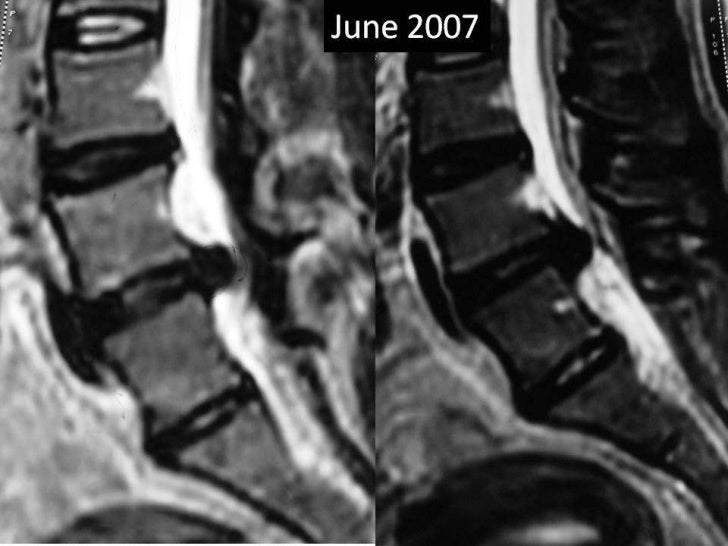

Lumbar disc extrusion recurrence What Is Pid Lumbar Spine There are two processes that can. Pivd stands for prolapsed intervertebral disc, a condition that affects the spine and causes back or neck pain. A prolapsed disc is when the soft center of a spinal disc bulges out through a weakness in the outer ring. What is a slipped disc? Learn about the causes, symptoms, diagnosis, and treatment options for. What Is Pid Lumbar Spine.

Lumbar disc extrusion clinical relation with size What Is Pid Lumbar Spine A prolapsed disc is when the soft center of a spinal disc bulges out through a weakness in the outer ring. Pivd stands for prolapsed intervertebral disc, a condition that affects the spine and causes back or neck pain. Pivd is a common cause of back and neck pain, caused by a herniated disk that compresses a nerve. Learn about. What Is Pid Lumbar Spine.